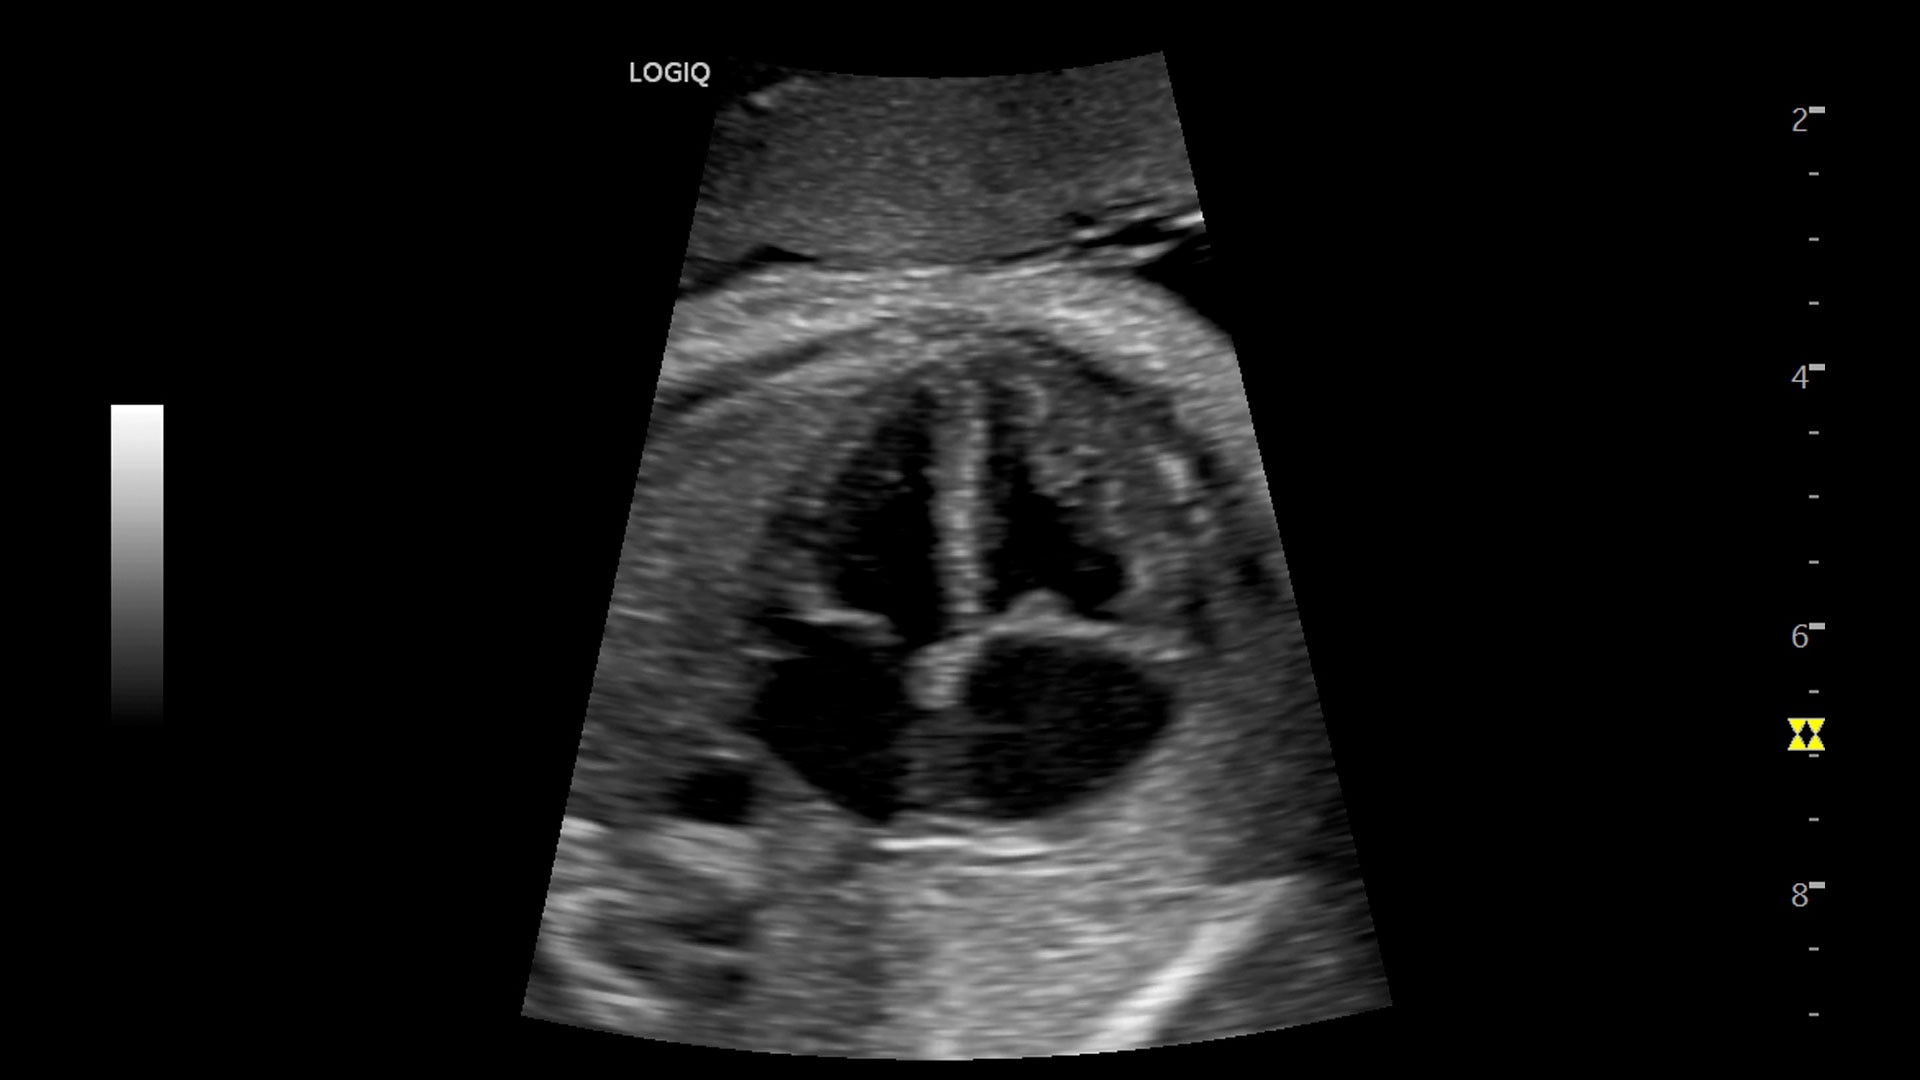

Multi-purpose capabilities, including liver, cardiac, OB/GYN, vascular, breast, thyroid, musculoskeletal, urologic, and pediatric studies.

Superb image quality with XDclear probes: Powerful high fidelity and broad bandwidth produce high resolution images whether scanning superficial or deep targets.

Advanced imaging and visualization tools, including:

• 3D/4D with SonoRenderlive